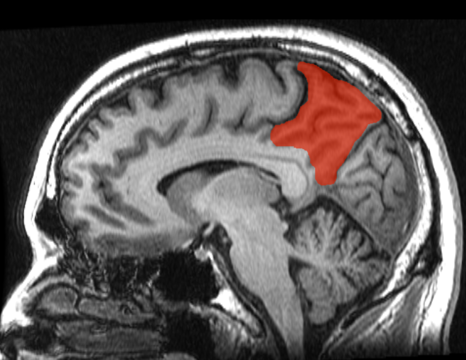

- le cortex frontal (ou lobe frontal) qui sert au langage, à la mémoire, au raisonnement et aux prises de décisions

- le cortex cingulaire antérieur qui joue un rôle dans les émotions, l'empathie et la prise de décision ;

- le précunéus (zone du lobe pariétal), une région servant à la représentation spatiale de l'environnement et à calculer à l'avance nos mouvements.